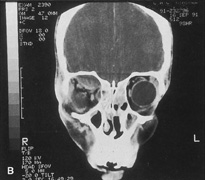

Procedure

The transcranial orbitotomy uses a frontal craniotomy with removal of a portion of the orbital roof to expose the orbital apex or superior orbit. This is best performed by a neurosurgeon familiar with skull-base surgical approaches. In most cases, the supraorbital rim over the involved side is removed en bloc with the frontal bone flap (Fig. 13). The anterior one-half or two-thirds of the orbital roof breaks free with removal of the rim and frontal bone flap, and the remaining posterior portion of the roof can be removed with rongeurs. Historically, it was suggested that all orbital tumors be removed via craniotomy, because before the imaging era it was difficult to anticipate the intraorbital location of a mass.18 The transfrontal approach was first described by Jones10 in 1970. Jane and colleagues19 proposed the current technique in 1982. Refinements have been discussed by Maroon and Kennerdell9 and Housepian.20 This operation has been termed the panoramic orbitotomy by Rootman21 because of the wide area of exposure offered by this procedure.

Fig. 14. A,B. Large intraorbital lymphangioma causing proptosis and optic nerve compression in a 2-year-old child. C. View of the left orbit from above after removal of the frontal bone flap, including the supraorbital rim and orbital roof. An extensive exposure of the entire superior and lateral orbit is afforded. The levator and superior rectus complex is being retracted laterally with a muscle hook, whereas the Freer elevator retracts the superior oblique muscle medially. The frontal nerve can be seen running from posterior to anterior over the superior orbit. The orbital mass is exposed in this fashion. D. The fronto-orbital bone flap is wired back in place after completion of the procedure. E. Postoperative appearance of the patient. F. The postoperative CT scan shows complete removal of the lymphangioma. This large and diffuse lesion would have been difficult to remove with any other approach.